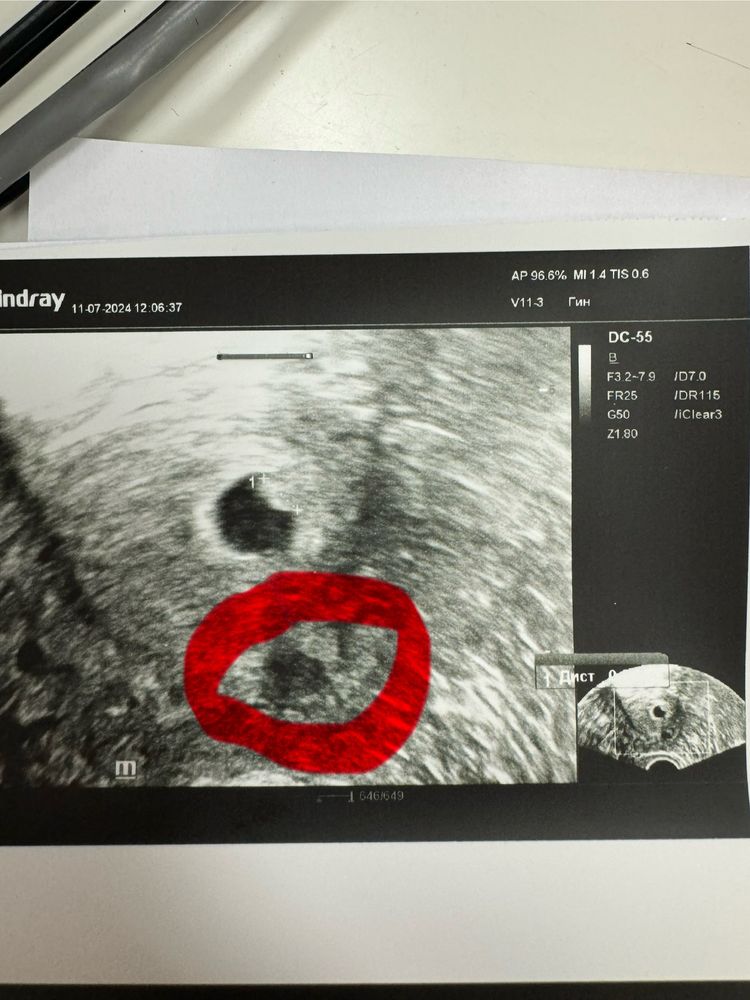

Что появилось на УЗИ?

Это отражение узи датчика и ничего более , так что не переживайте .

Сложно даже понять это в миометрии или за пределами матки) может миомка небольшая, может узелок аденомиоза🤷🏻‍♀️ если вам не описали это в заключении-вряд ли это что-то важное